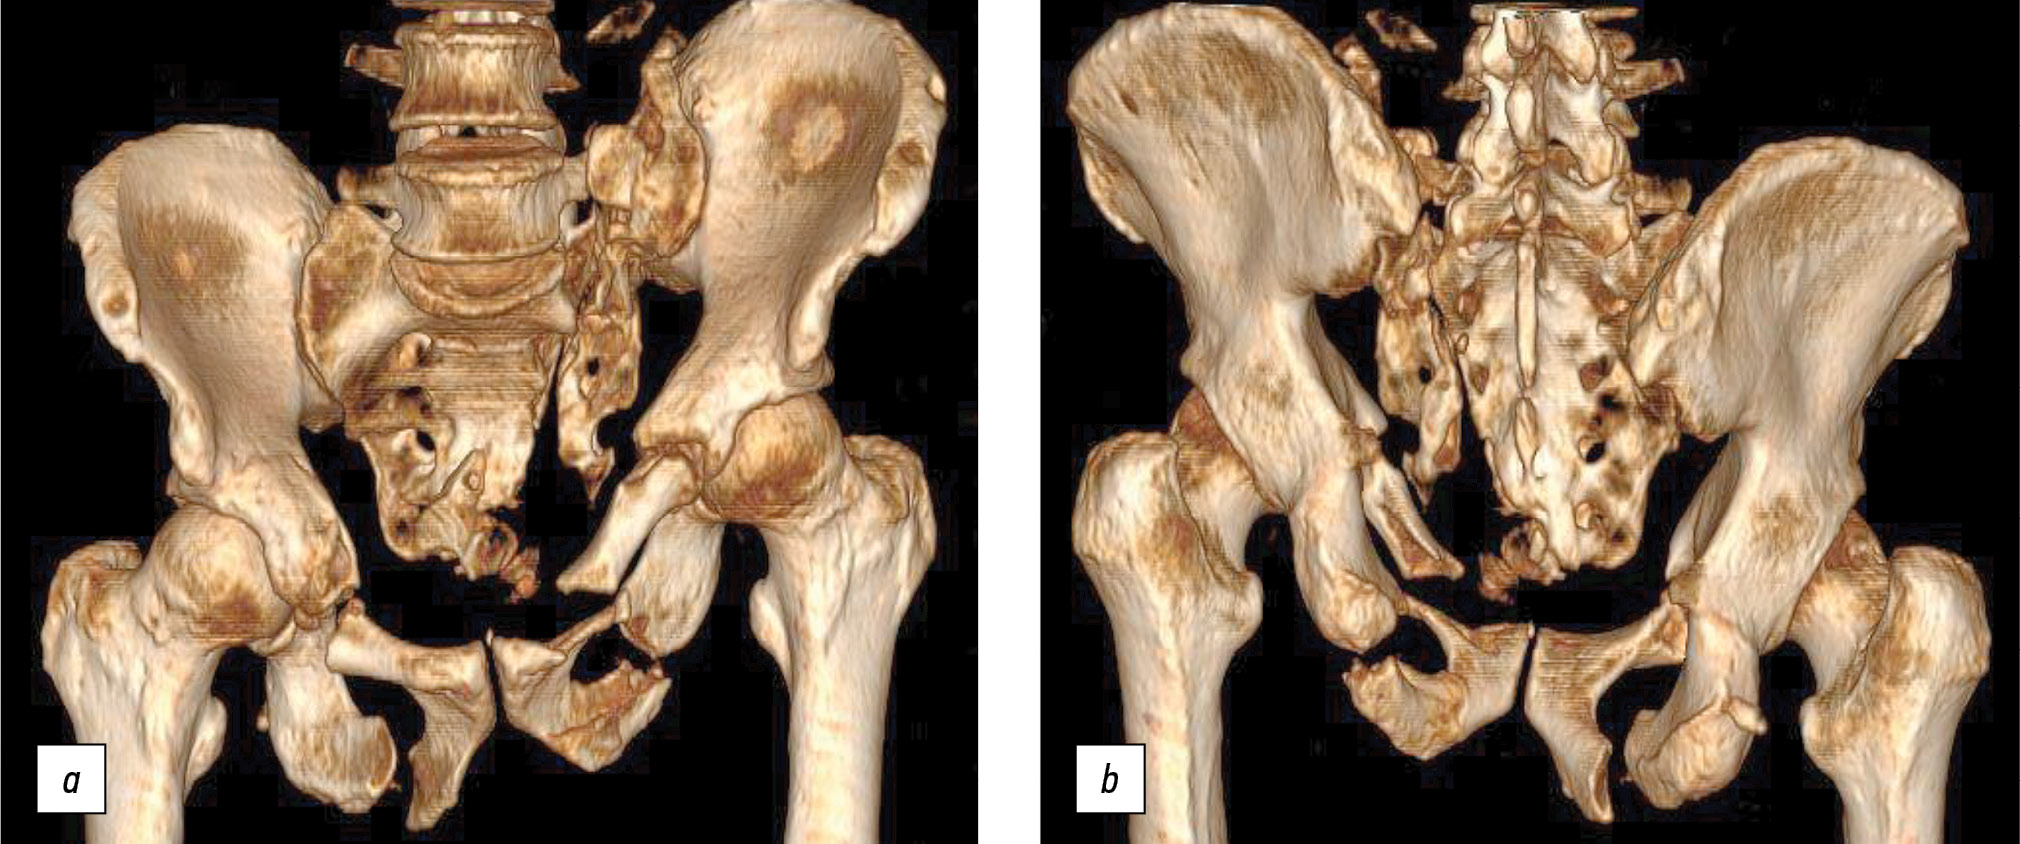

To assess the stability of the pelvic ring, all patients underwent functional pelvic X-ray imaging with alternating loading of the left and right lower extremities (Fig. 1).

Fig. 1. Functional radiography from the pelvis with alternating load on the left and right lower extremities. а — standing on the left leg; b — standing on the right leg.